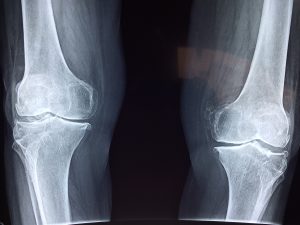

Osteoporosis is often called a “silent disease” because bone loss occurs gradually and without apparent symptoms. Some people may experience mild bone pain, especially in the hips or feet, but many don’t realize anything is wrong until a fracture occurs. Early screening for osteoporosis can play a crucial role in preventing significant injury.2Porter JL, Varacallo MA. Osteoporosis. In: StatPearls. StatPearls Publishing; 2025. Accessed April 29, 2025. http://www.ncbi.nlm.nih.gov/books/NBK441901

Fractures are the most serious consequence of osteoporosis. Hip fractures, in particular, often require surgery, lengthy hospital stays, and ongoing rehabilitation. They can lead to lasting disability and even increased risk of death. Only about 33 percent of senior women who experience a hip fracture are able to return to independent living. Worse still, one hip fracture significantly raises the risk of having another.

Spinal fractures can happen with or without a fall and are often followed by chronic back pain, reduced mobility, and noticeable changes in posture.2Porter JL, Varacallo MA. Osteoporosis. In: StatPearls. StatPearls Publishing; 2025. Accessed April 29, 2025. http://www.ncbi.nlm.nih.gov/books/NBK441901